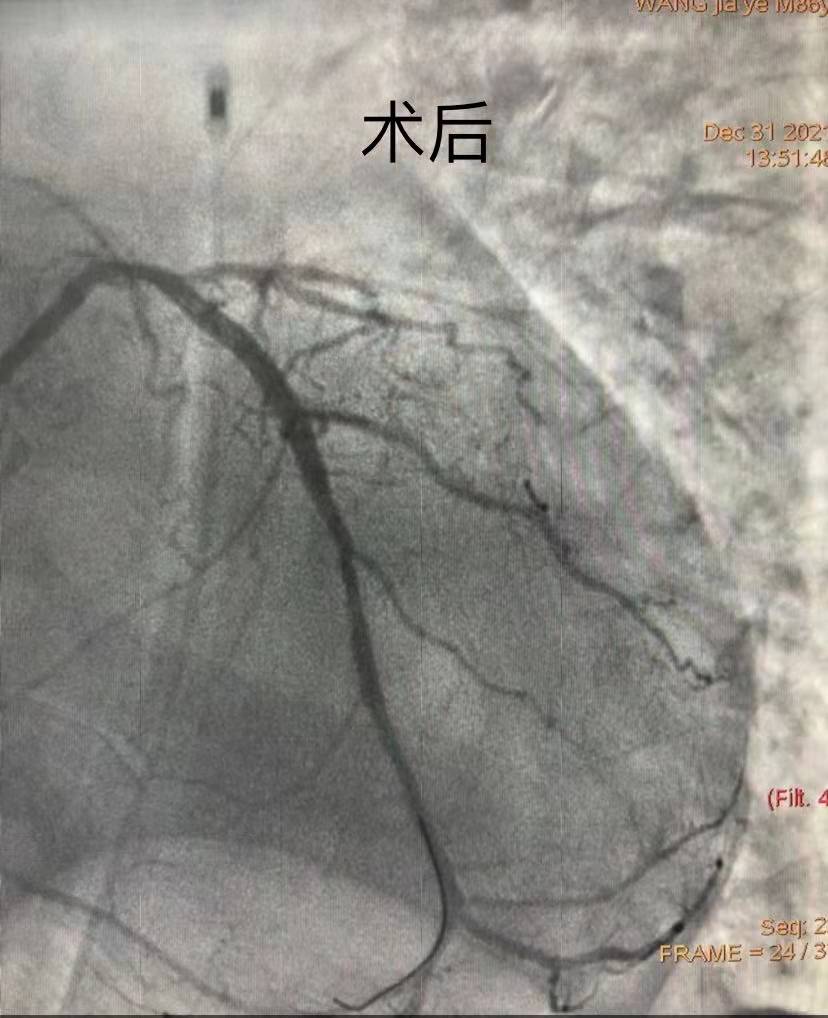

團(tuán)隊(duì)綜合考慮后判斷,LCX是此次心肌梗死的“元兇”。開(kāi)通病變部位的機(jī)會(huì)只有一次,必須做到“快、準(zhǔn)、狠”。汪院長(zhǎng)團(tuán)隊(duì)經(jīng)驗(yàn)豐富,技術(shù)嫻熟,導(dǎo)絲小心通過(guò),球囊充分?jǐn)U張,最后在病變部位植入支架,所有操作一氣呵成。復(fù)查造影顯示,病變部位狹窄小于10%,手術(shù)獲得成功。